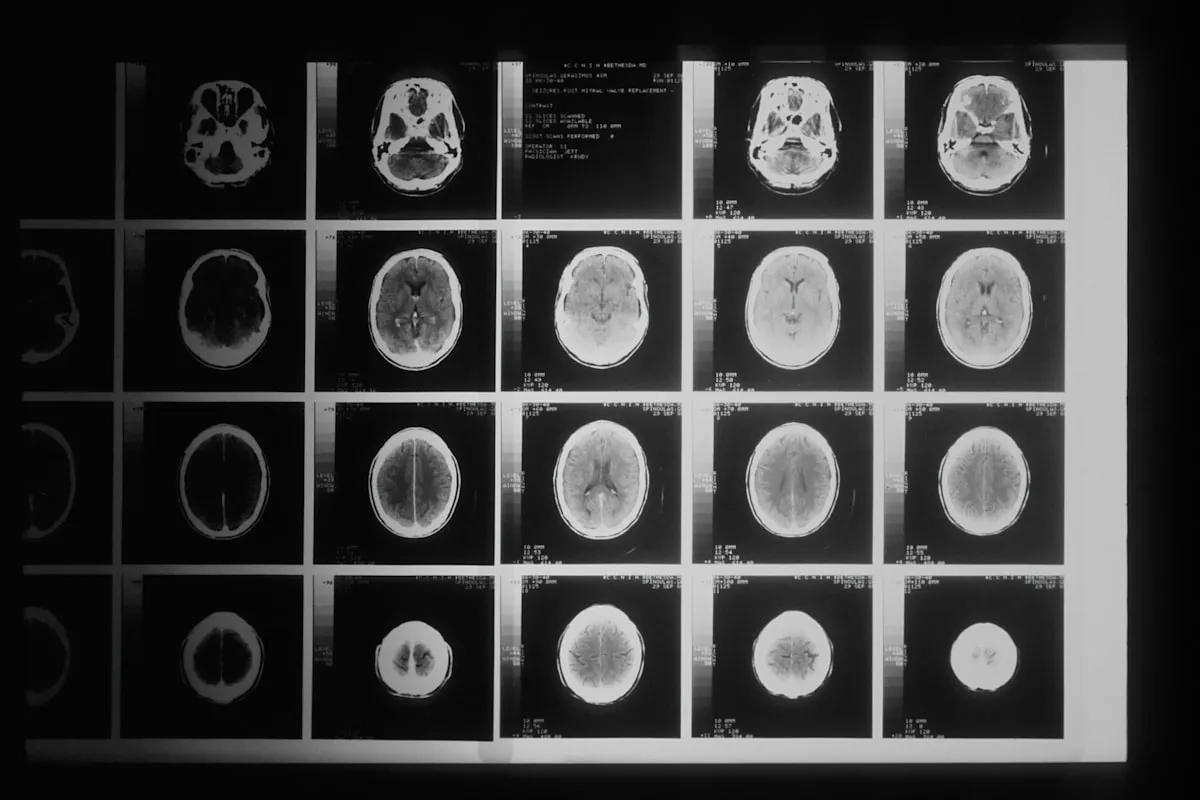

画像診断支援AI

医療AIのなかで最も導入が進んでいるのが画像診断支援です。AIが医用画像を解析し、病変の見落としを防ぐ「第二の目」として機能します。最終的な診断はあくまで医師が行いますが、AIによる支援で診断精度が向上した事例が多数報告されています。

- 胸部X線の肺結節検出(EIRL Chest Nodule / エルピクセル):薬機法承認済み。X線画像から肺結節を自動検出し、医師に通知

- 大腸内視鏡の病変検出(EndoBRAIN-EYE / オリンパス):薬機法承認済み。病変発見率98%の事例あり。2024年度から診療報酬加算の対象(内視鏡AI加算60点)

- 脳卒中CTトリアージ(RapidAI):PMDAクラスIII承認取得。国内18施設で3,400例以上の実績。搬送直後のCT画像からAIが脳卒中を判定し、緊急度をトリアージ

- 咽頭検査AI(nodoca / Aillis):薬機法承認済みで保険診療に対応。AI感度76.0%・特異度88.1%。1,000を超える施設で導入済み

- 骨折検出(富士フイルム):肋骨骨折を自動検出

- 眼底検査(OUI Inc.):スマホを用いた眼科AI診断

2. 診断精度の向上・見落とし防止

画像診断支援AIは、医師の「第二の目」として見落としリスクを軽減します。とくに内視鏡検査では、EndoBRAIN-EYEで病変発見率98%を達成した事例が報告されています。ただし、AIはあくまで補助であり、最終判断は医師が行う点は変わりません。